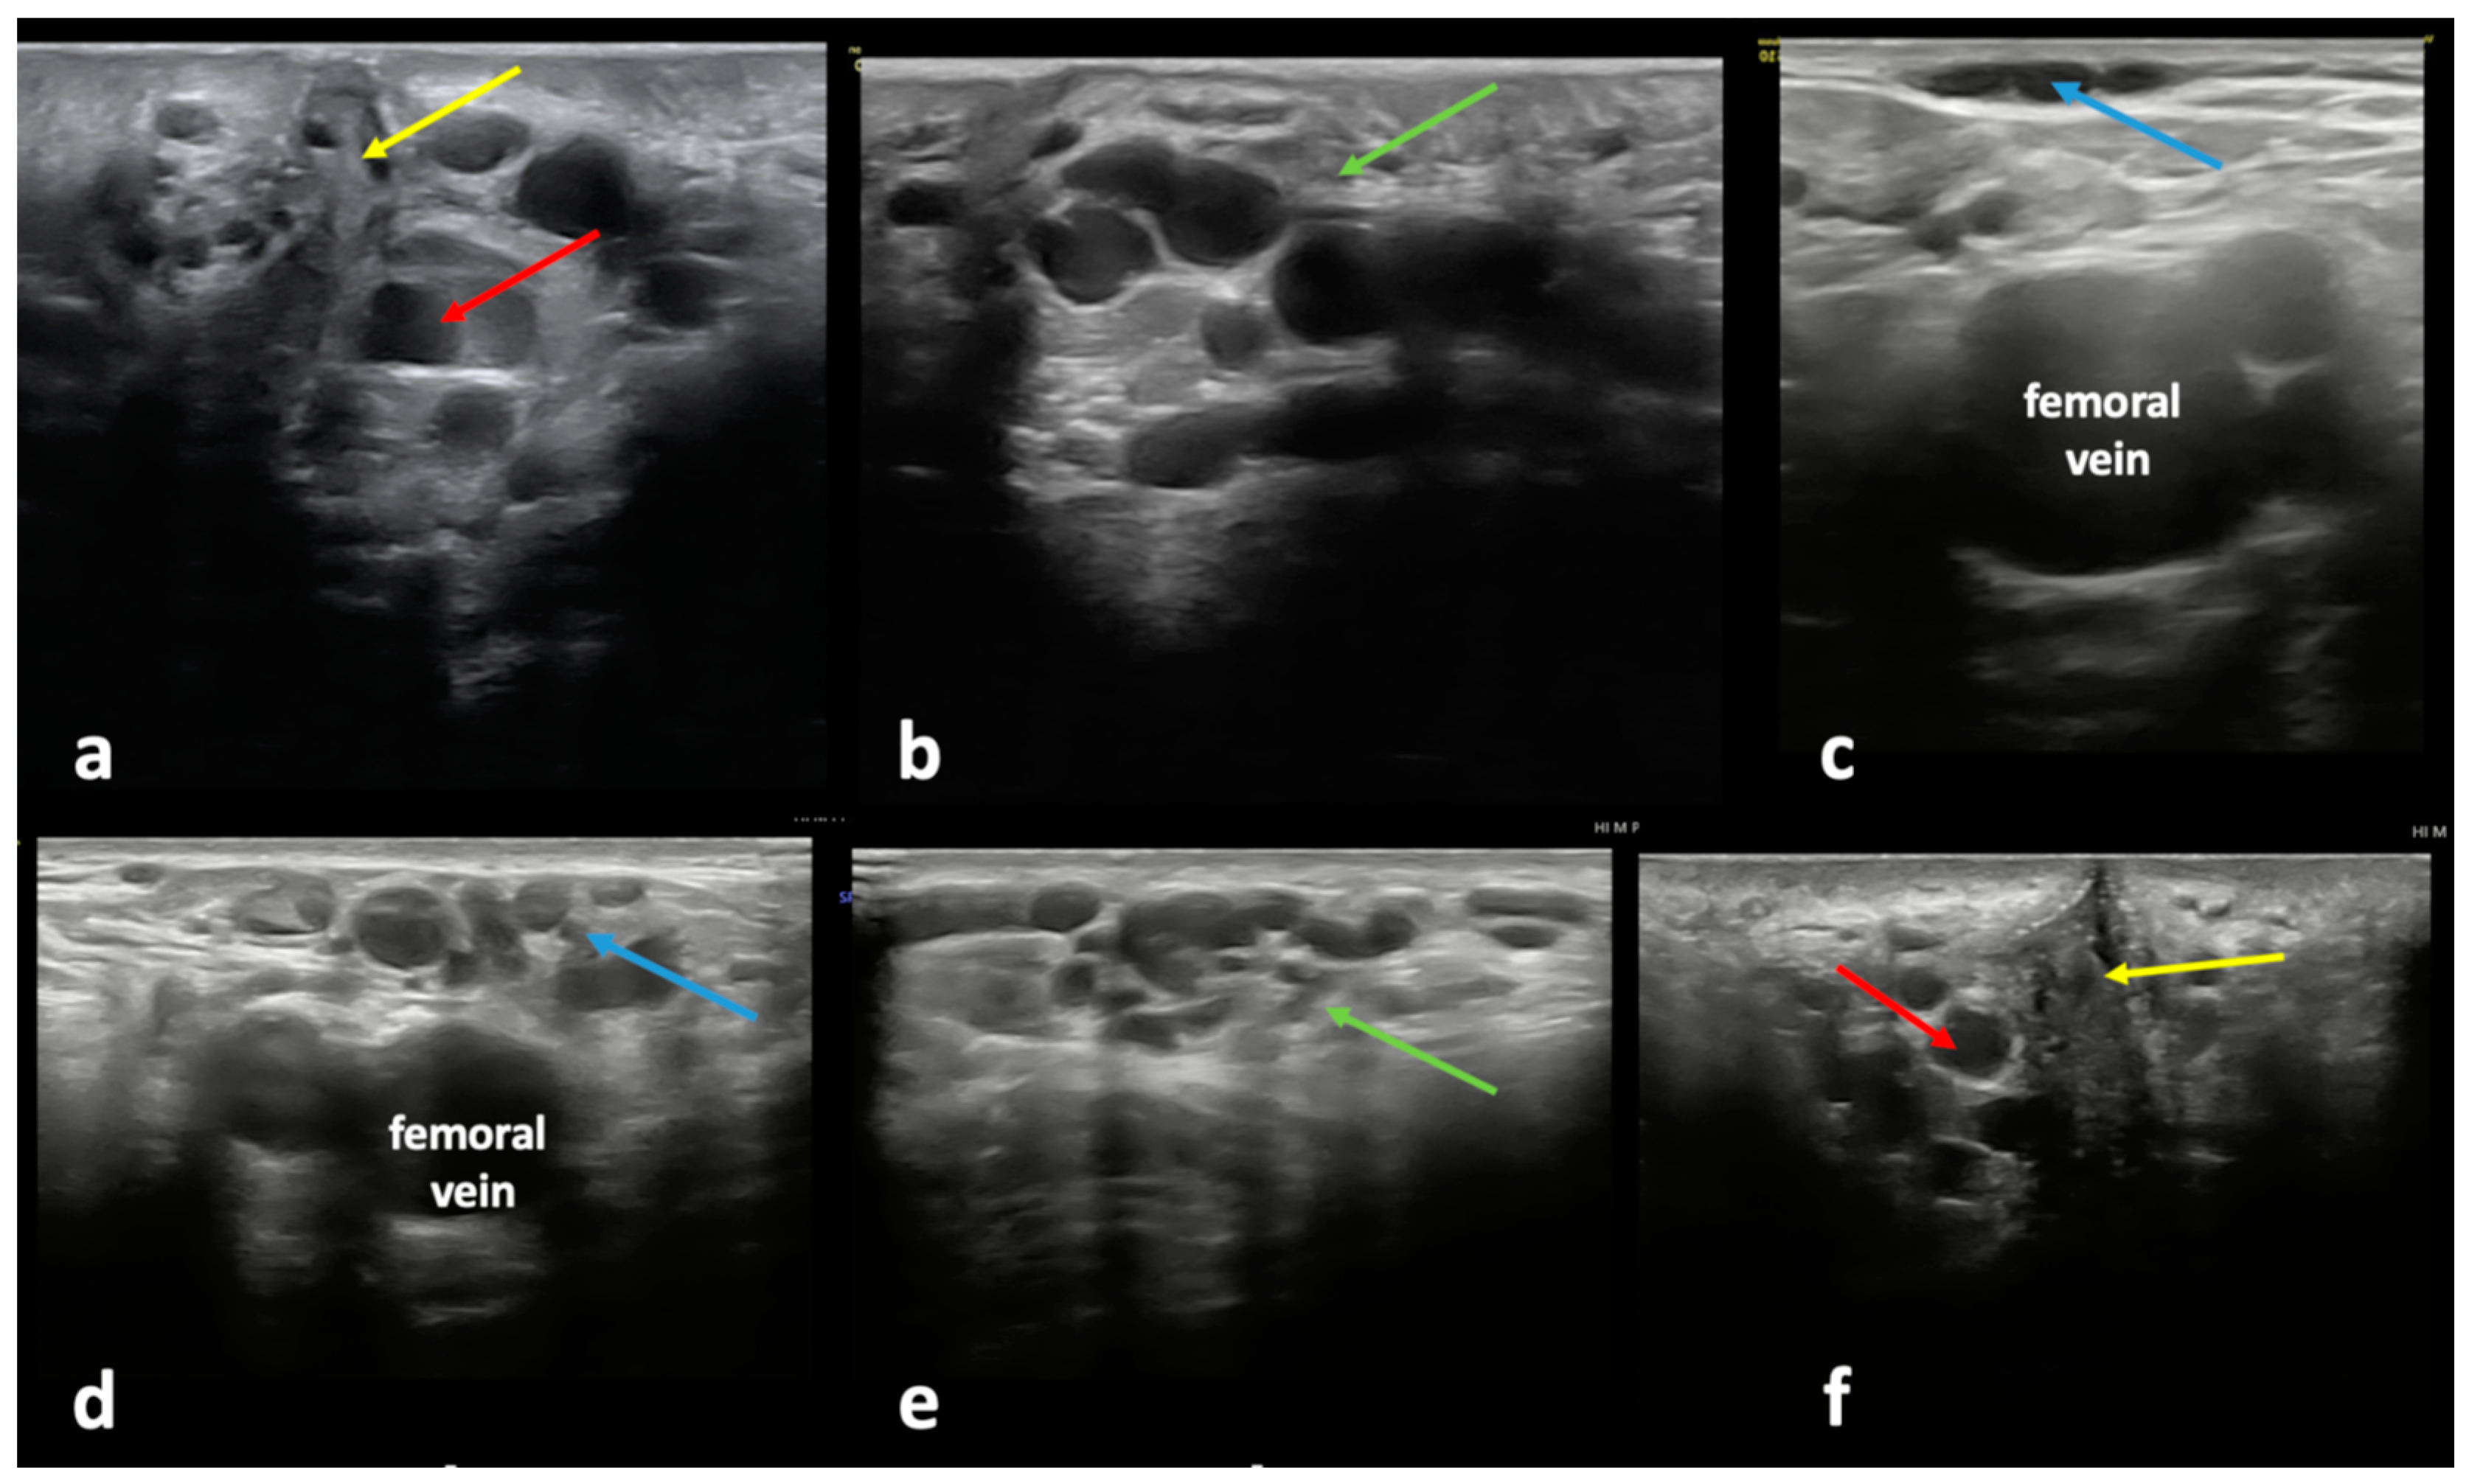

4.1.1. Clitoral Escape Point

Figure 4. Ultrasonographic assessment of the clitoral pelvic escape point and related varicose veins (VVs): incompetent clitoral pelvic escape point (red arrow) on the (a) left and (f) right side of the clitoris (yellow arrow), resulting in (b,e) a dilated and incompetent external pudendal vein (green arrow) forming VV clusters at the mons pubis and the inguinal area, causing (c,d) atypical VVs (blue arrow) at the anterior aspect of the thigh.